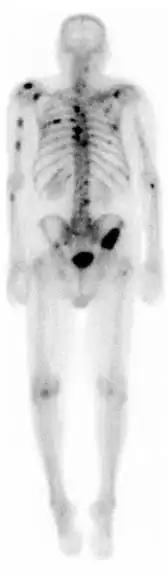

A nuclear medicine whole-body bone scan. The nuclear medicine whole-body bone scan is generally used in evaluations of various bone-related pathology, such as for bone pain, stress fracture, nonmalignant bone lesions, bone infections, or the spread of cancer to the bone.